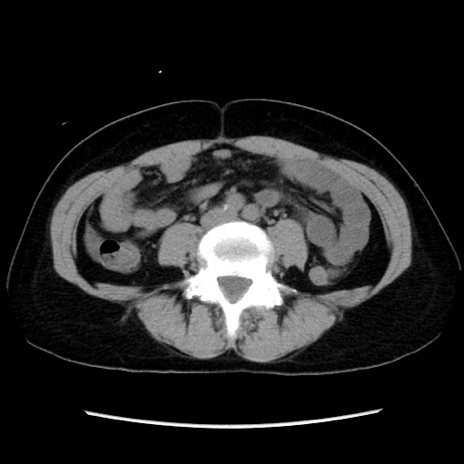

症例10(横断像)

【症例】 50歳代女性

【主訴】 腹痛

【現病歴】前日生レバーを食べた。今朝に排便あり。 昼前に突然発症の腹痛を生じ、当院救急外来を受診した。

【身体所見】 意識清明、腹部:平坦、軟、下腹部やや左を中心に圧痛・反跳痛あり、筋性防御あり

【データ】WBC 7800、CRP 0.07